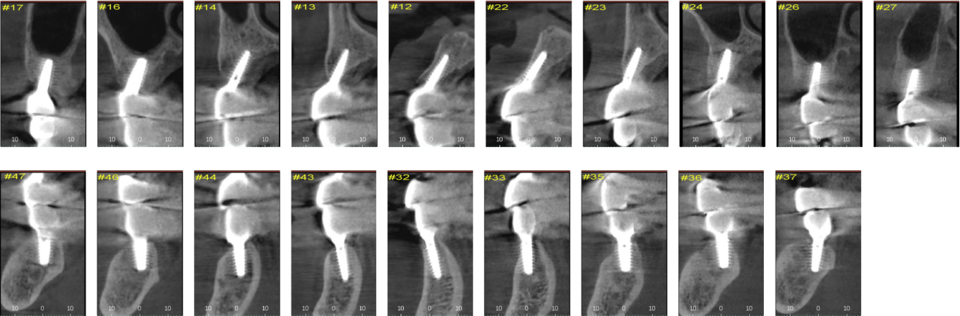

본 증례에서는 치아의 평균 근원 심 폭경을 참고하여 캘리퍼로 근원심 간격을 표시한 후 Magic Guide Pin을 꼽고 [그림 2]

CBCT를 촬영하여 식립 예정부위의 치조골 상태와 식립 방향을 분석하여 flapless 시술법으로 상악에 10개, 하악에는 좌측 견치의 발치 즉시 식립을 포함하여 8개의 MagiCore를 2일에 걸쳐 식립하였다 [그림 3~4].